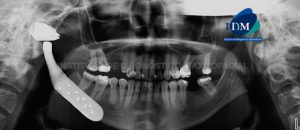

Paciente femenino de 24 años de edad, es referido al Instituto de Diagnóstico Maxilofacial – IDM por accidente. En la radiografía panorámica (Figura 1) se